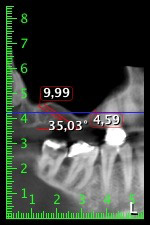

The 59-year-old patient presented with an advanced case of periodontitis, describing an unpleasant feeling and poor taste from the first quadrant in a distal direction. The clinical examination revealed generally enlarged periodontal pockets and very advanced bone atrophy in regions 16 and 14. The radiology confirmed the findings (Fig. 1). Teeth 16 and 14 could not be retained.

About six months after teeth 16 and 14 were extracted, a digital volume tomography (DVT, Planmeca) examination was performed for planning and risk minimization purposes. It clearly showed that the bone had not regenerated to the desired volume (Fig. 2 to 7).